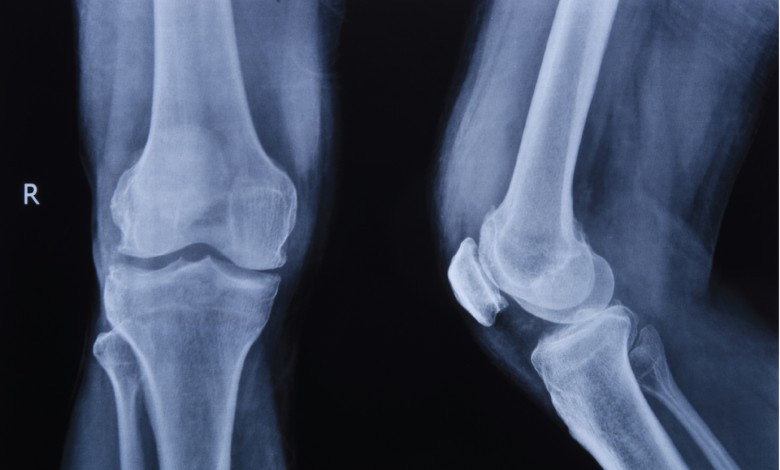

รศ.พล.อ.ท.นพ.จำรูญเกียรติ ลีลเศรษฐพร แพทย์เฉพาะทางกระดูกและข้อ จากโรงพยาบาลเอส เฉพาะทางกระดูกสันหลังและข้อ (S Spine and Joint Hospital) อธิบายว่า ข้อเข่าเป็นข้อต่อขนาดใหญ่ที่ต้องรับน้ำหนักของร่างกายตลอดเวลา ภายในข้อเข่าประกอบด้วยกระดูกอ่อน เอ็น กล้ามเนื้อ และกระดูกชิ้นสำคัญที่เรียกว่า “ลูกสะบ้า” (Patella) ซึ่งอยู่ด้านหน้าของข้อเข่า มีหน้าที่ช่วยเพิ่มแรงให้กล้ามเนื้อหน้าขาในการเหยียดเข่า และช่วยให้การเคลื่อนไหวของข้อเข่าเป็นไปอย่างราบรื่น

เมื่อเกิดภาวะข้อเข่าเสื่อม กระดูกอ่อนที่ทำหน้าที่รองรับแรงกระแทกจะค่อย ๆ สึกหรอ โดยเฉพาะบริเวณใต้ลูกสะบ้าที่ต้องรับแรงกดและแรงเสียดสีสูง ส่งผลให้เกิดอาการปวดเข่าด้านหน้า มักปวดชัดเจนเวลาขึ้นลงบันได ลุกนั่ง หรือใช้งานข้อเข่าเป็นเวลานาน